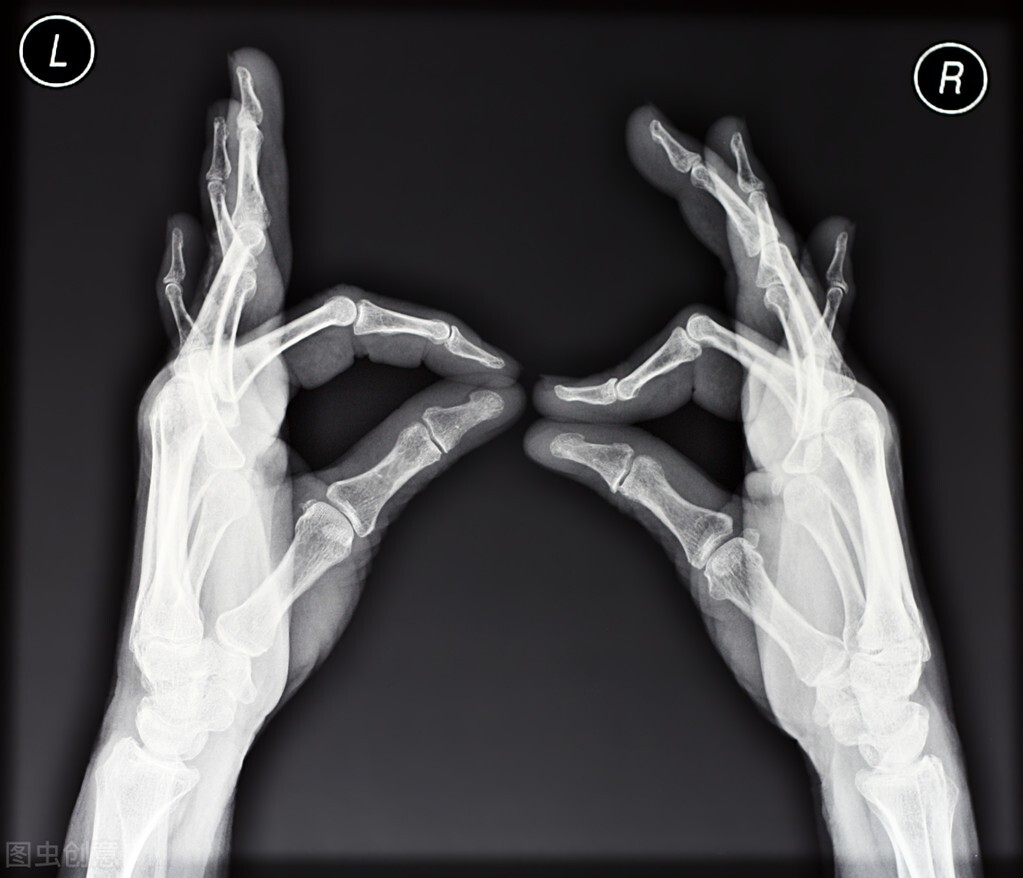

类风湿关节炎以近端指间关节、掌指关节、腕关节最为常见,关节畸形也最常发生在这些关节,常见的畸形包括:

- 纽扣花畸形 ——手指近端指间关节屈曲,远端指间关节过伸,整体看上去手指像纽扣花。

- 天鹅颈畸形 ——手指近端指间关节过伸,远端指间关节屈曲,侧面看手指的形状像天鹅的颈部。

- 尺侧偏斜畸形 ——拇指以外的四指,掌指关节都向小指方向(尺侧)偏斜。

- 望远镜畸形 ——指骨骨端吸收导致手指明显缩短,手指关节松弛不稳,可拉长或缩短,所以称为望远镜畸形。

当这些畸形出现时,意味着患者的关节内部已经发生严重的破坏,即便是通过关节镜微创治疗,这些关节变形也无法恢复,所以,对付畸形的唯一出路,就是预防畸形的出现。为此,患者要及早发现病情,并及时到正规医院就医,同时与医生良好沟通和密切配合,进行正确、规范的治疗,不要陷入“秘方”“偏方”的误区。